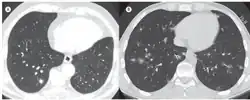

| In A, axial CT scan of the chest showing a right lower lobe pulmonary nodule surrounded by areas of ground-glass opacity (the CT halo sign). In B, axial CT scan of the chest showing multiple, randomly distributed pulmonary nodules surrounded by the CT halo sign; the final diagnosis was aspergillosis. | |

The halo sign is also understood as a region of ground-glass attenuation surrounding a pulmonary nodule on an X-ray computed tomography (CT scan) of the chest. It can be associated with hemorrhagic nodules, tumors, or inflammatory processes, but is most commonly known as an early radiographic sign of invasive pulmonary infection by the fungus species Aspergillus.